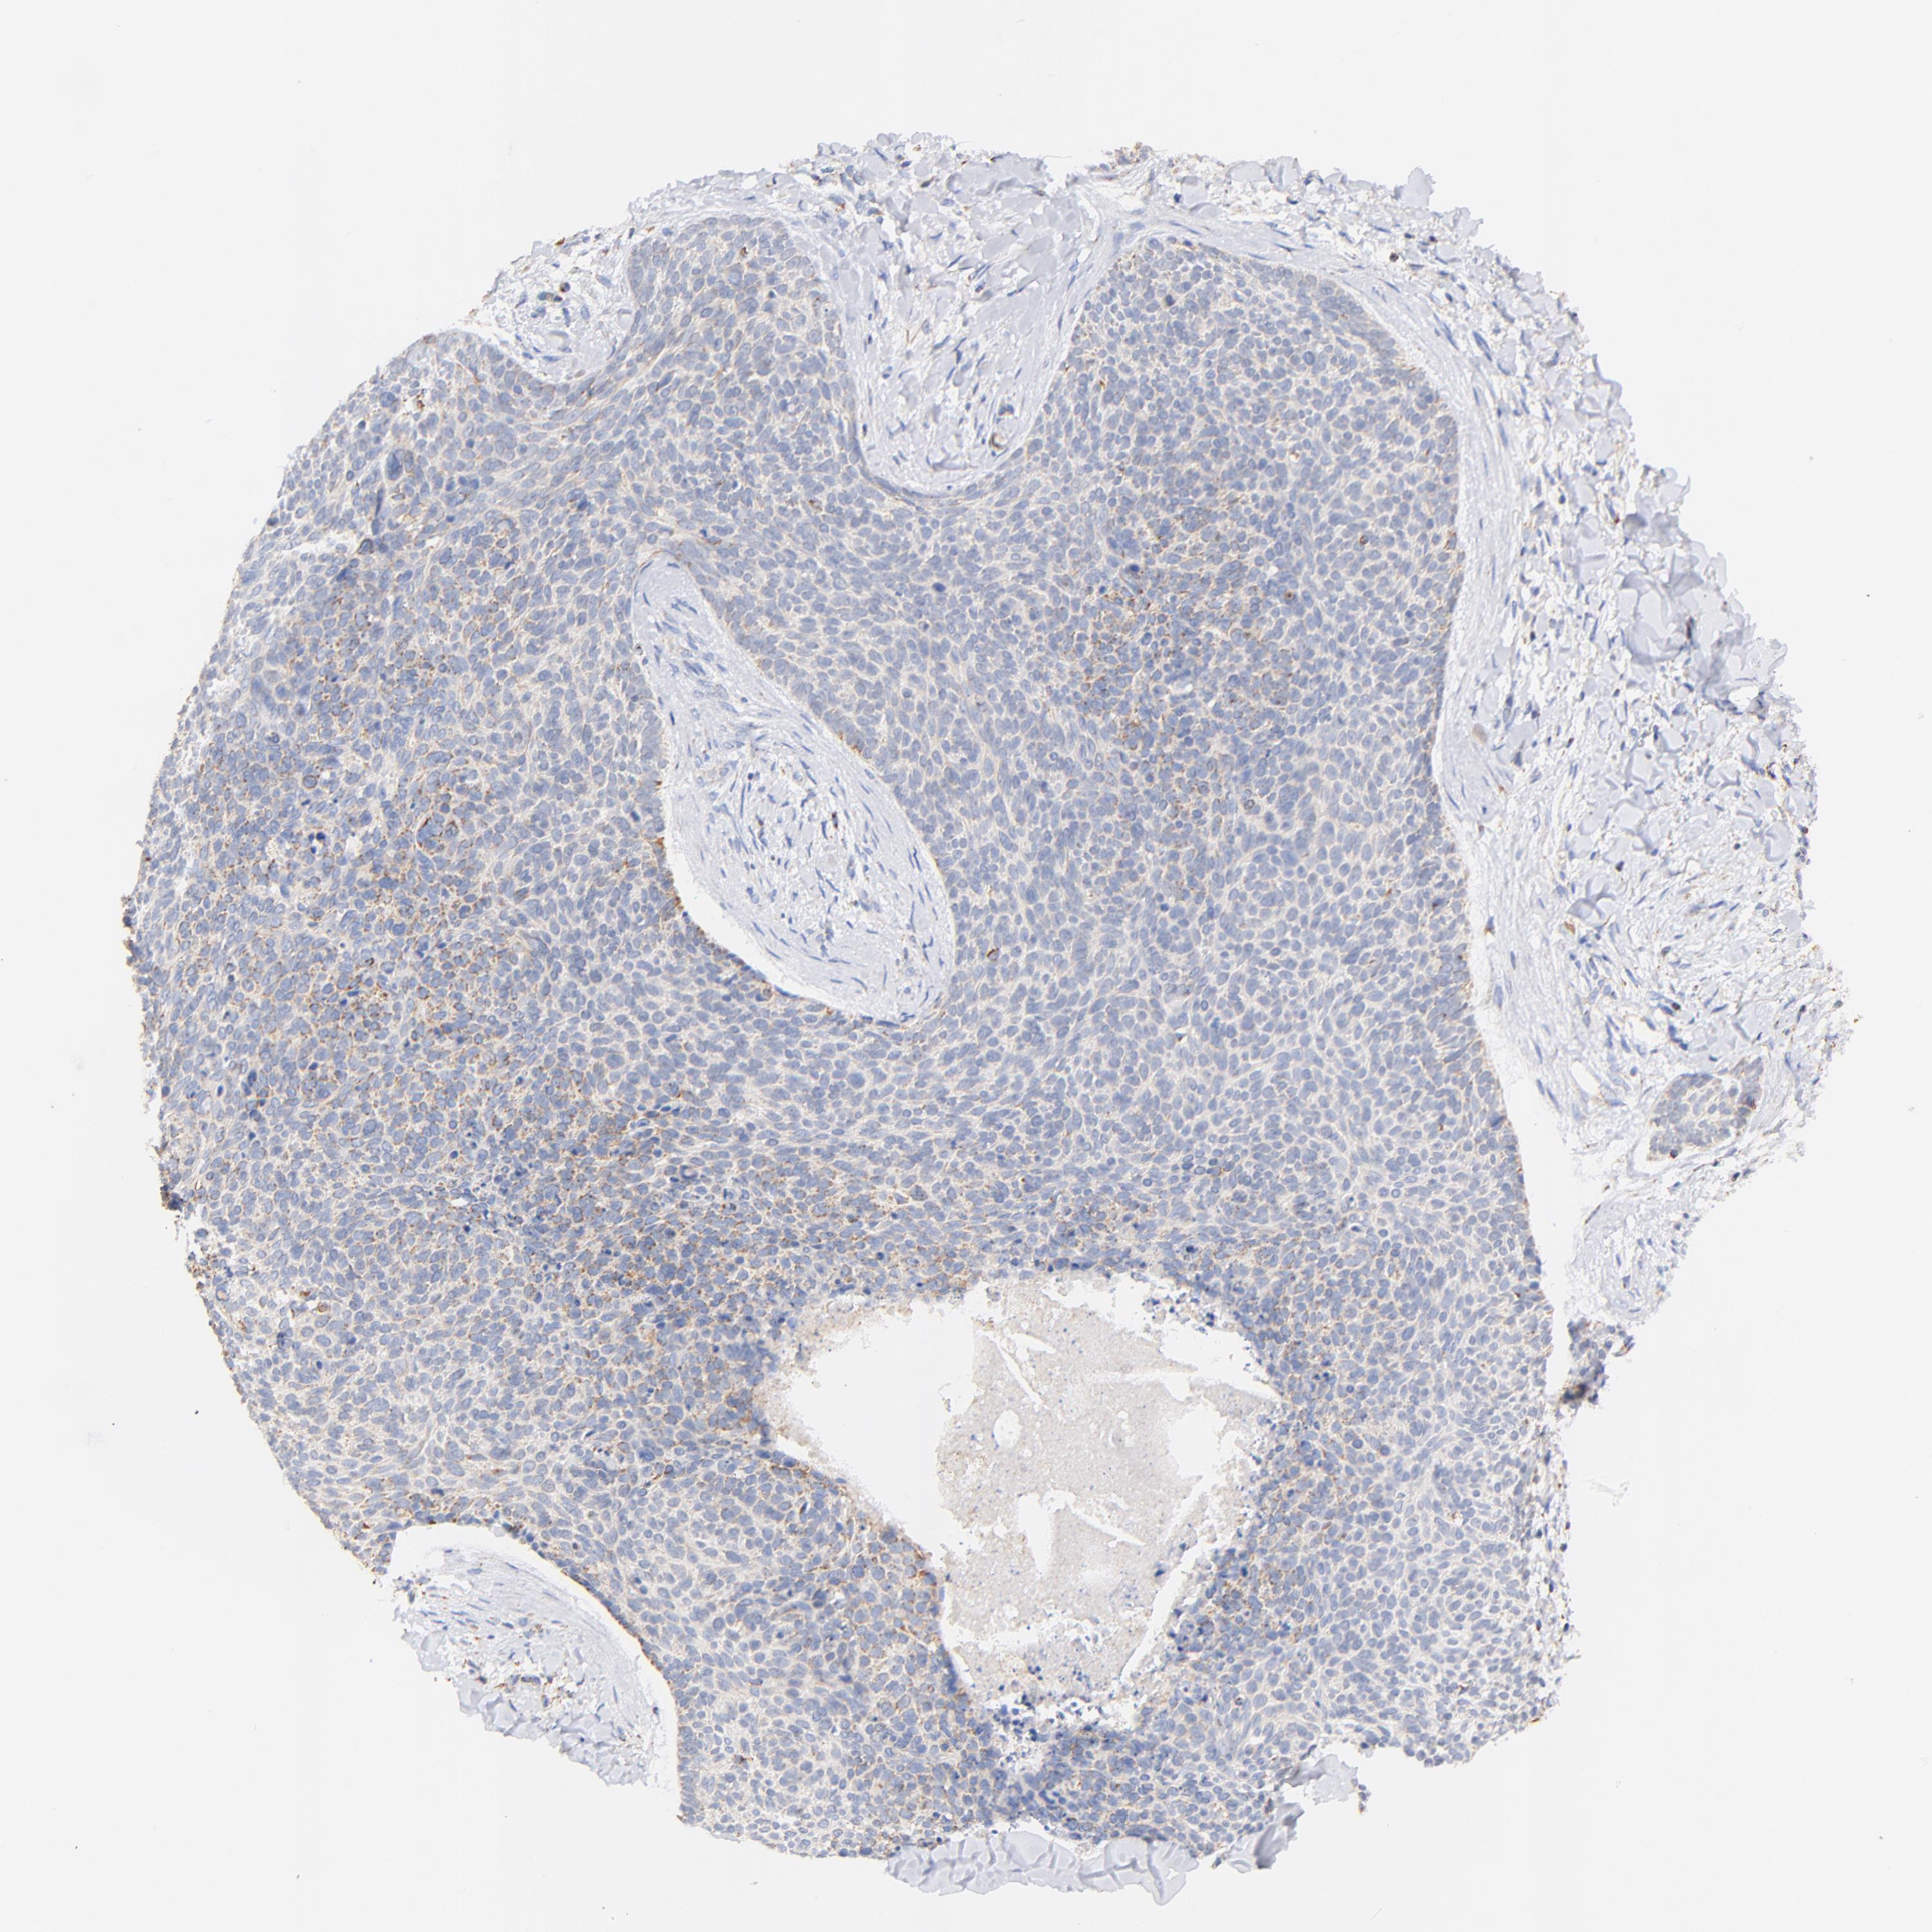

Basal cell and squamous cell cancer

SKIN CANCER - Protein expressioni

A mouse-over function shows sample information and annotation data. Click on an image to view it in a full screen mode. Samples can be filtered based on level of antibody staining by selecting one or several of the following categories: high, medium, low and not detected. The assay and annotation is described here.

Antibody stainingi

Antibody staining in the annotated cell types in the current human tissue is reported as not detected, low, medium, or high, based on conventional immunohistochemistry profiling in selected tissues. This score is based on the combination of the staining intensity and fraction of stained cells.

Each image is clickable and will lead to virtual microscopy that enables deeper exploration of all samples and also displays staining intensity scores, fraction scores and subcellular localization as well as patient and tissue information for each sample.

Antibody HPA002865

Staining

High

Medium

Low

Not detected

Intensity

Strong

Moderate

Weak

Negative

Quantity

>75%

75%-25%

<25%

None

Location

Nuclear

Cytoplasmic/membranous

Cytoplasmic/membranous,nuclear

Squamous cell carcinoma, NOS

Basal cell carcinoma